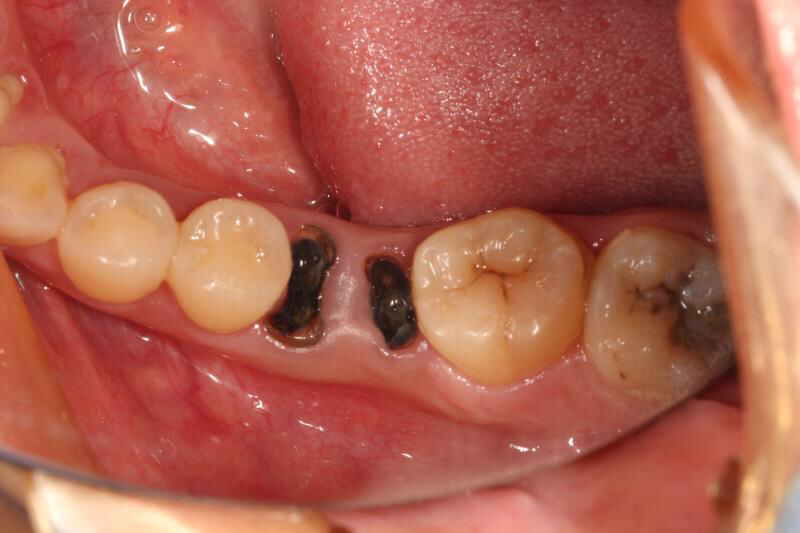

今天给大家介绍一个单颗后牙种植+局部正畸联合治疗病例。

患者年轻女性,后下6残根,因未及时修复,5、7号牙向6号牙倾斜,导致了修复空间不足。按照常规治疗方案,会损伤两侧的健康牙齿,得不偿失,所以我们为她采用了正畸+种植联合治疗方案。